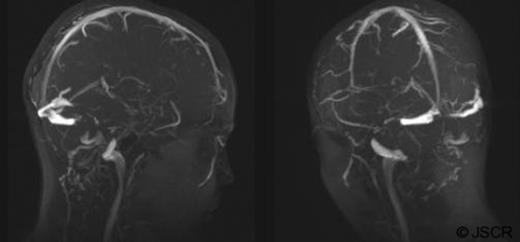

An MRI brain with venography (MRV) sequences provided greater anatomical delineation (figure 1). Despite a coincidental finding of a smaller calibre left venous sinus; thrombus was not seen to extend intracranially. Lastly an echocardiogram was sought confirming a normal heart with no septal defects, vegetations or thrombus.

MRV brain images demonstrate bilateral sagittal, straight, transverse and sigmoid sinuses with no evidence of thrombus extension. Both right and left IJV as well as right EJV are clearly patent. The left EJV could not be demonstrated.